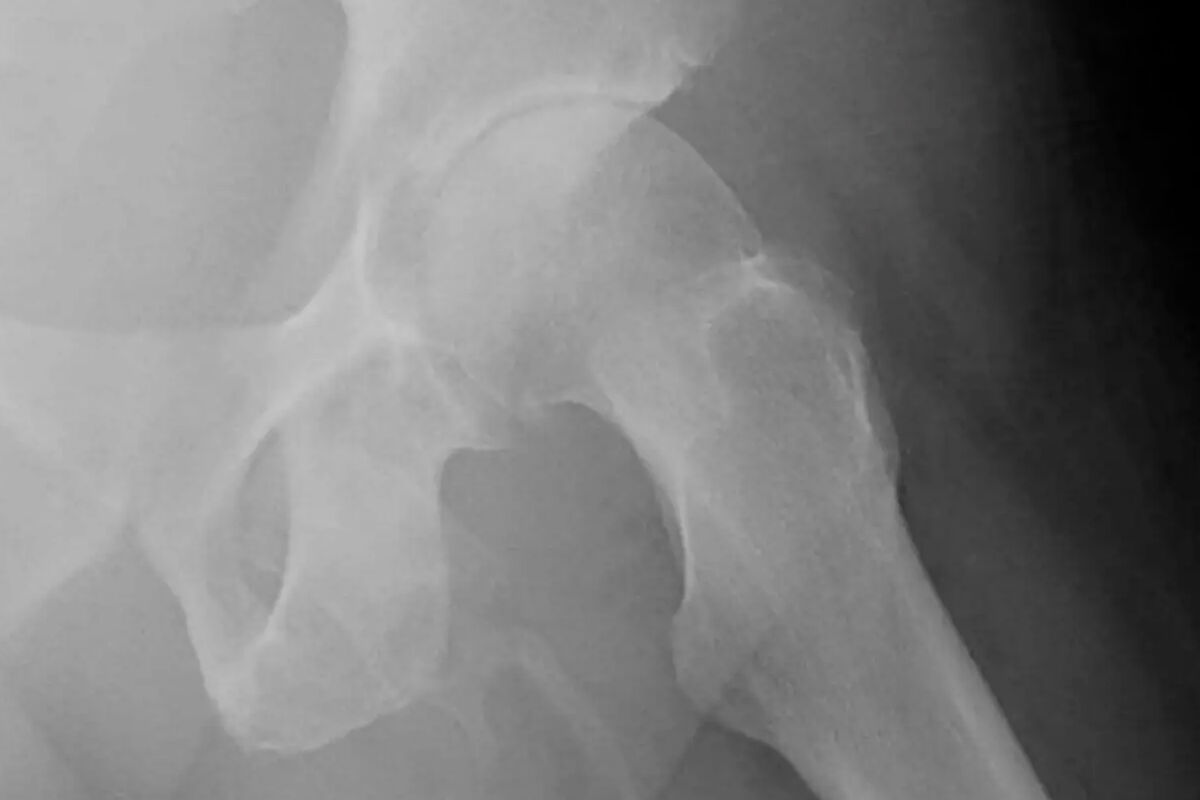

Как сообщают СМИ, 63-летний мужчина обратился в больницу Нью-Йорка с жалобами на боль в левом колене после падения на тротуар. Пациента отправили на рентген, потому что врачи подозревали у него возможный перелом в бедренной кости, что и могло быть причиной дискомфорта. Однако вместо перелома врачи обнаружили нечто гораздо более необычное – у мужчины образовалась «внескелетная кость» в пенисе.

По словам специалистов, эта костеподобная кальцификация накапливалась в мягких тканях вдоль пениса американца, делая его твердым, как кость. Сам процесс простыми словами называется окостенением полового члена и является чрезвычайно редким заболеванием, которое наблюдается менее чем у 40 человек в мире.